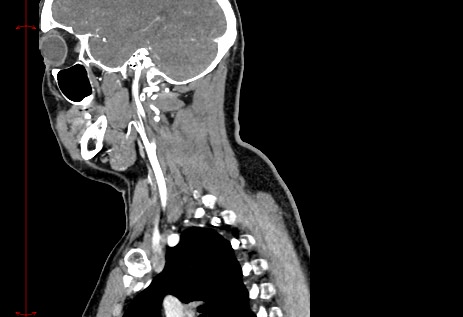

Мультиспиральная КТ сосудов шеи (КТ-ангиография) включает в себя сканирование брахиоцефальных артерий, то есть как сосудов кровоснабжающих головной мозг, так и проксимальные отделы плечевых артерий. Это крупные сосуды, которые отходят от дуги аорты и, разветвляясь, уходят в полость черепа. К ним относятся: брахиоцефальный ствол, общие, наружные и внутренние сонные артерии, подключичные и позвоночные артерии.

КТ сосудов шеи является высокоинформативным методом диагностики патологии брахиоцефальных артерий, который позволяет выявлять участки сужения, патологической извитости, определять развитие атеросклеротических бляшек ещё до того, как появились симптомы заболевания.

В наших медицинских центрах диагностика патологии магистральных сосудов шеи проводится на современных мультиспиральных компьютерных томографах экспертного уровня TOSHIBA AQUILION. Компьютерная томография относится к лучевым методам исследования, то есть для получения изображения внутренних органов используется рентгеновское излучение. Трубка томографа при помощи рентгеновских лучей послойно сканирует область исследования с минимальной толщиной среза от 0,5 мм, затем полученные данные трансформируются в объемные изображения. Оснащение аппаратов позволяет получать снимки и трехмерные реконструкции сосудистой системы превосходного качества, при этом пациент получает минимальную дозу облучения.

Для улучшения визуализации сосудистой системы обязательным является проведение контрастного усиления. Для этого пациенту внутривенно вводится йодсодержащий контрастный препарат, который активно поглощает рентгеновские лучи и обеспечивает яркую видимость даже мелких сосудов на фоне окружающих тканей.